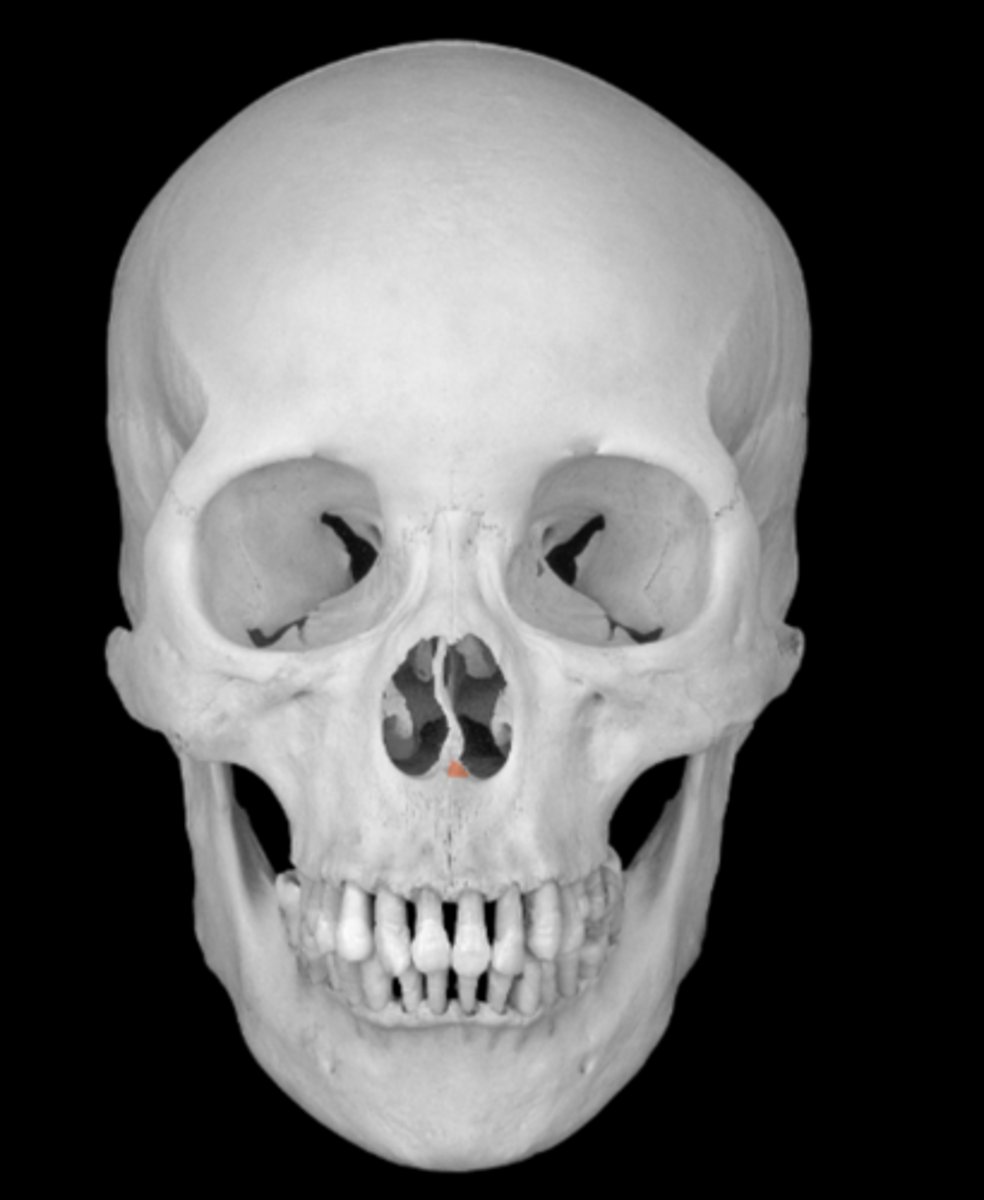

Maxilla Bone

maxilla bone

nasal aperture of maxillae

intermaxillary suture of maxillae

alveolar process of maxillae

dental alveoli of the maxilla

zygomatic process of maxillae

frontal process of the maxilla

orbital surface of the maxilla

infraorbital margin of the maxilla

infraorbital foramen of maxilla

anterior nasal spine of maxilla

maxillary sinus of maxilla

lacrimal groove of maxilla

anterior lacrimal crest of maxilla